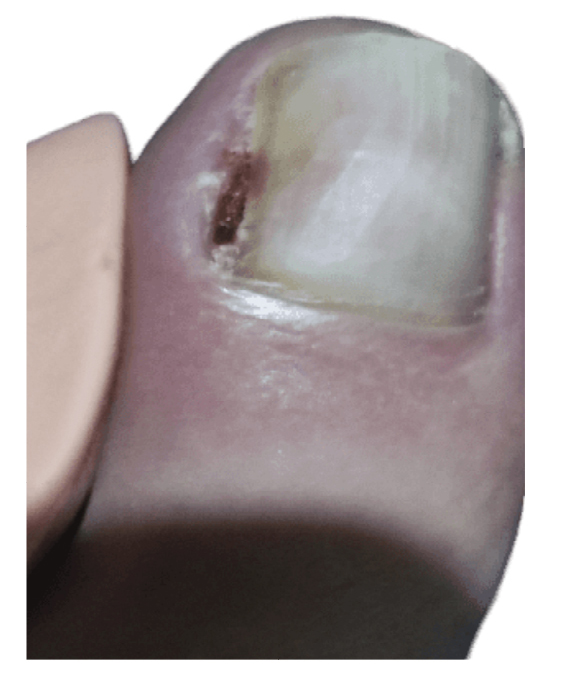

La paciente refiere proceso de inicial de onicocriptosis de 7 meses de evolución (septiembre de 2022), en el borde medial del primer dedo del pie izquierdo, con la presencia de tejido de granulación ungueal en dicho borde, el cual le produce dolor e inflamación digital (Figura 1). La paciente recibe tratamiento por su podólogo que consiste en quiropodia y limpieza del canal; se pautan posteriormente curas diarias con mupirocina para la lesión. Existe mala evolución de la lesión en los días siguientes con aumento de dolor y sensibilidad al tacto. Se modifica el tratamiento pautando amoxicilina/ácido clavulánico 875/125 mg, 1/8 h junto con el uso de analgésicos orales (Figura 2). La paciente continúa con mala evolución sintomatológica y acude a su centro de salud donde se realiza radiografía con la cual se descarta la presencia de infección profunda (osteomielitis).

Figura 1. Proceso inicial de onicocriptosis y granuloma reactivo.